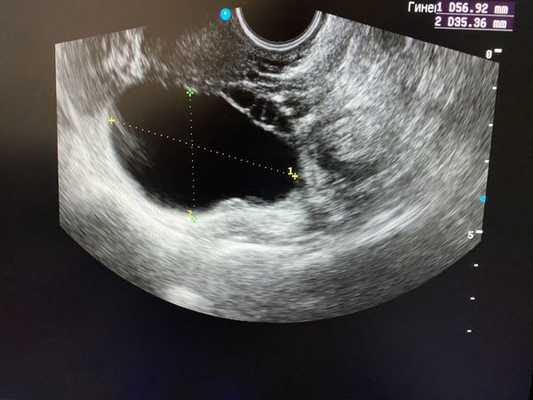

Безусловно, проведение ультразвуковой диагностики трансабдоминальным и трансвагинальным датчиками позволит не только выявить локализацию кисты, но и определить ее структуру, размеры, характер жидкостного содержимого, определить тактику лечения пациентки. Особенностью фолликулярных кист при ультразвуковом исследовании является тонкостенная капсула с отсутствием сосочков внутренней стороны капсулы. [10] Диагностировать кистозные образования у беременных женщин значительно труднее, ввиду увеличения размеров матки на соответствующих сроках беременности, поэтому ультразвуковое исследование стоит проводить с ЦДК и доплерометрией [11] .

При ультразвуковом исследовании влагалищным или абдоминальным датчиком определяется округлое тонкостенное образование с однородным содержимым, которое выглядит тёмным пятном. Иногда внутри определяется мелкодисперсная взвесь.

Важным критерием, указывающим на параовариальную кисту, является незатронутый яичник, который видно при УЗИ.